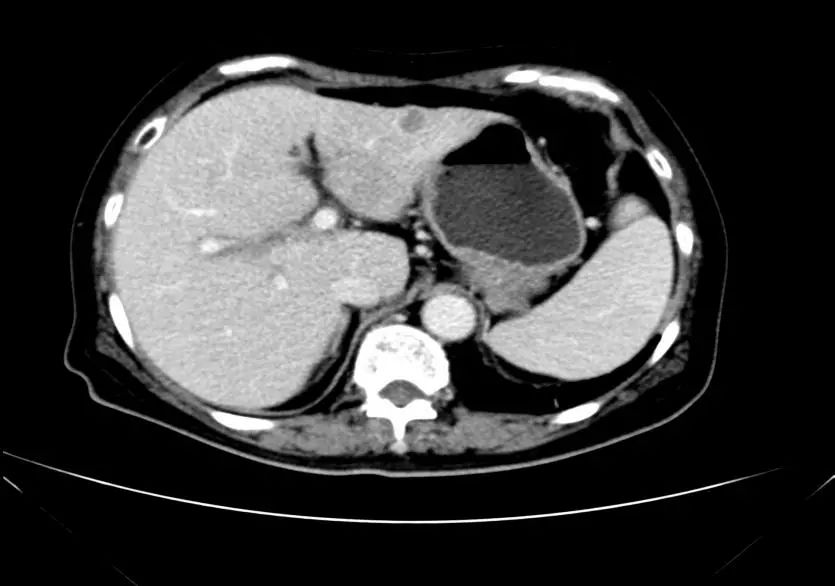

影像学表现:

影像学检查结果评估:cPD。

疗效评估:cPR

TOGA研究是第一个使用HER2抑制剂曲妥珠单抗治疗不能手术的局部晚期、复发或转移的HER2阳性胃癌患者的Ⅲ期临床研究。TOGA研究结果显示,IHC2+/FISH阳性或者IHC3+的患者与对照组相比,OS分别为16.0个月和11.8个月(HR为0.65)。曲妥珠单抗联合化疗显著提高了HER2阳性晚期转移性胃癌的治疗缓解率和总体生存率。2012年8月,曲妥珠单抗治疗HER2阳性转移性胃癌适应症在我国获批。对该患者进行病理切片会诊,幸运的是其HER2检测为阳性。随即进行靶向联合化疗治疗,三个周期后,肝转移灶消失,曲妥珠单抗治疗效果显著。九个周期的靶向治疗联合放化疗后,疗效评估cPR,随即行手术治疗。